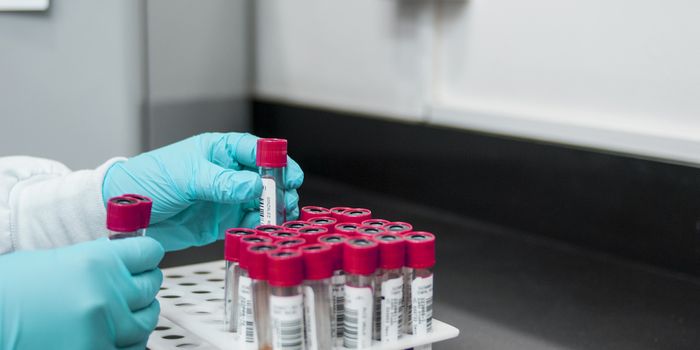

FEB 08, 2016Clinical & Molecular DXAccording to researchers from the National Institute of Health (NIH), a simple blood test may soon be able to detect fiv ...

JAN 18, 2016Clinical & Molecular DXWhen cells die, their genetic contents are released into bodily fluids through a process known as autolysis. In the rece ...

FEB 22, 2016Clinical & Molecular DXResearchers have developed a new blood test that can survey all 174 of known genes involved in 17 inherited heart condit ...